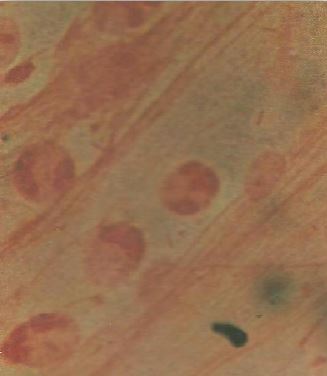

مريض يستعمل القسطرة فجأة بدأ يظهر عليه حمى وحموضة وانخفاض في ضغط الدم وقلة مرات التبول oliguria. عينة الدم أظهرت مجهرياً (الشكل 1) تم عزل نفس الكائن المسبب للمرض من عينة البول وعرف كيموحيوياً على أنه الجنس البكتيري Klebsiella Spp .

الشكل رقم 1 الكشف المجهري